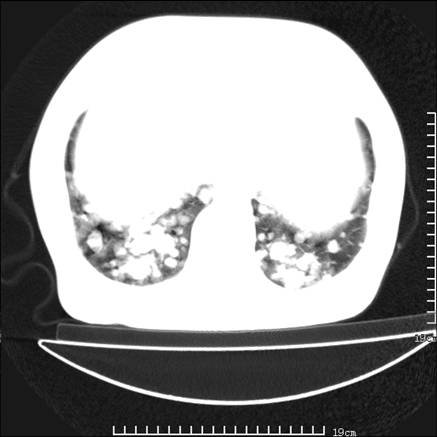

张男,75岁,干咳半年余,小便不利二年,b超检查前列腺增大,未见明显肿块;前列腺癌血生化检查多项指标明显增高。

双肺内多发转移瘤,纵膈淋巴结转移。来源前列腺?建议盆腔mri进一步检查。

双肺转移满了。

两肺广泛转移瘤。